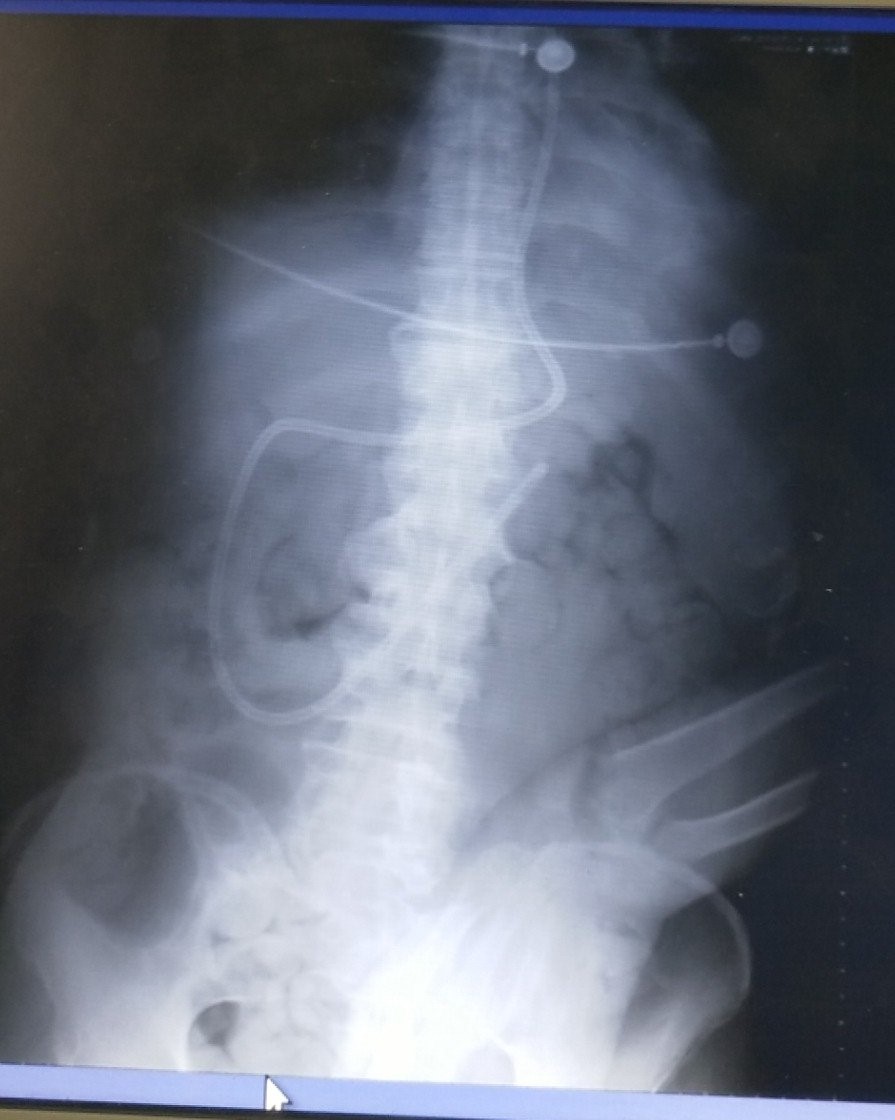

85岁男性老年患者,因“脑出血后遗症”合并肺炎,收治入院。老人病史现已气管切开,吞咽功能消失,不能经口进食,长期胃管喂养出现腹胀反流,只能靠静脉营养补充热量,这使老人身心饱受煎熬。对于危重患者来说,在血流动力学稳定后,尽早启动肠内营养是促进患者度过危重期的必要条件。考虑患者目前身体状况,床旁盲插鼻肠管,是满足患者肠内营养进食需求的最理想途径,在与主管医生和家属沟通后,由ICU护士长栗春杰为老人实施床旁盲插经鼻空肠营养管植入技术,整个过程非常顺利,患者目前生命体征平稳,治疗效果非常明显。

据悉,肠内营养是重症患者营养支持的主要方式之一,主要分为鼻胃营养和鼻肠营养两种。对于使用呼吸机、反流误吸高风险患者以及昏迷、无法经口进食等患者,使用鼻肠营养不仅有助于促进肠道运动,维护肠道完整性,减少细菌的移位,降低能量的消耗与高代谢水平,减少反流现象,而且有效的肠内营养,还可以维护肠道粘膜屏障的完整性,降低肠源性感染的发生。而作为方法之一的床旁盲插置管法操作更方便、不需要多科协作,护士能直接在床旁完成操作,但是对操作者技术要求较高。我院栗春杰护士长凭借多年丰富的临床护理经验和扎实的理论知识,成功完成了此次床旁盲插鼻空肠管操作技术,不仅解决了危重患者肠内营养的问题,还大大提高了危重患者救治的成功率,标志我院护理技术水平迈向了一个新台阶。